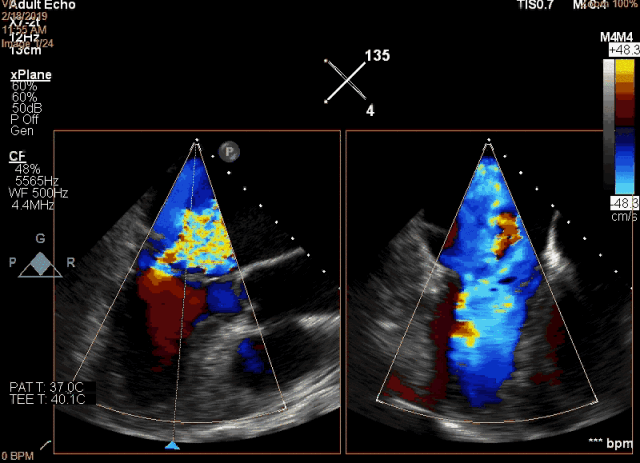

图2  术前食道超声显示二尖瓣大范围脱垂及极重度反流